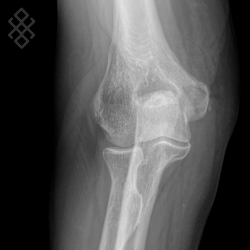

Radiographie du Coude

Positionnement

Vous serez installés en position debout avec le bras posé sur la table d'examen.